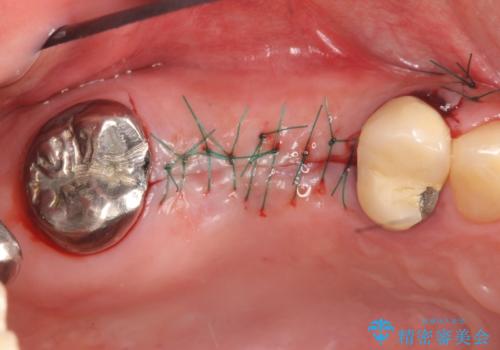

右上の567ブリッジを外したところ、右上5は歯根破折により保存不可能だったため、右上56部にインプラントを埋入し欠損補綴を行いました。

また右上5部に関しては抜歯時に歯槽堤保存術(抜歯窩に人工骨の填入を行う手術)を行い、骨の欠損を最小限に止めています。

- オールセラミッククラウン…¥100,000×2、仮歯…¥10,000×2、歯槽堤保存術…¥100,000、インプラント(ストローマン)…¥200,000×2、カスタムアバット…¥100,000×2費用は治療当時の料金となります